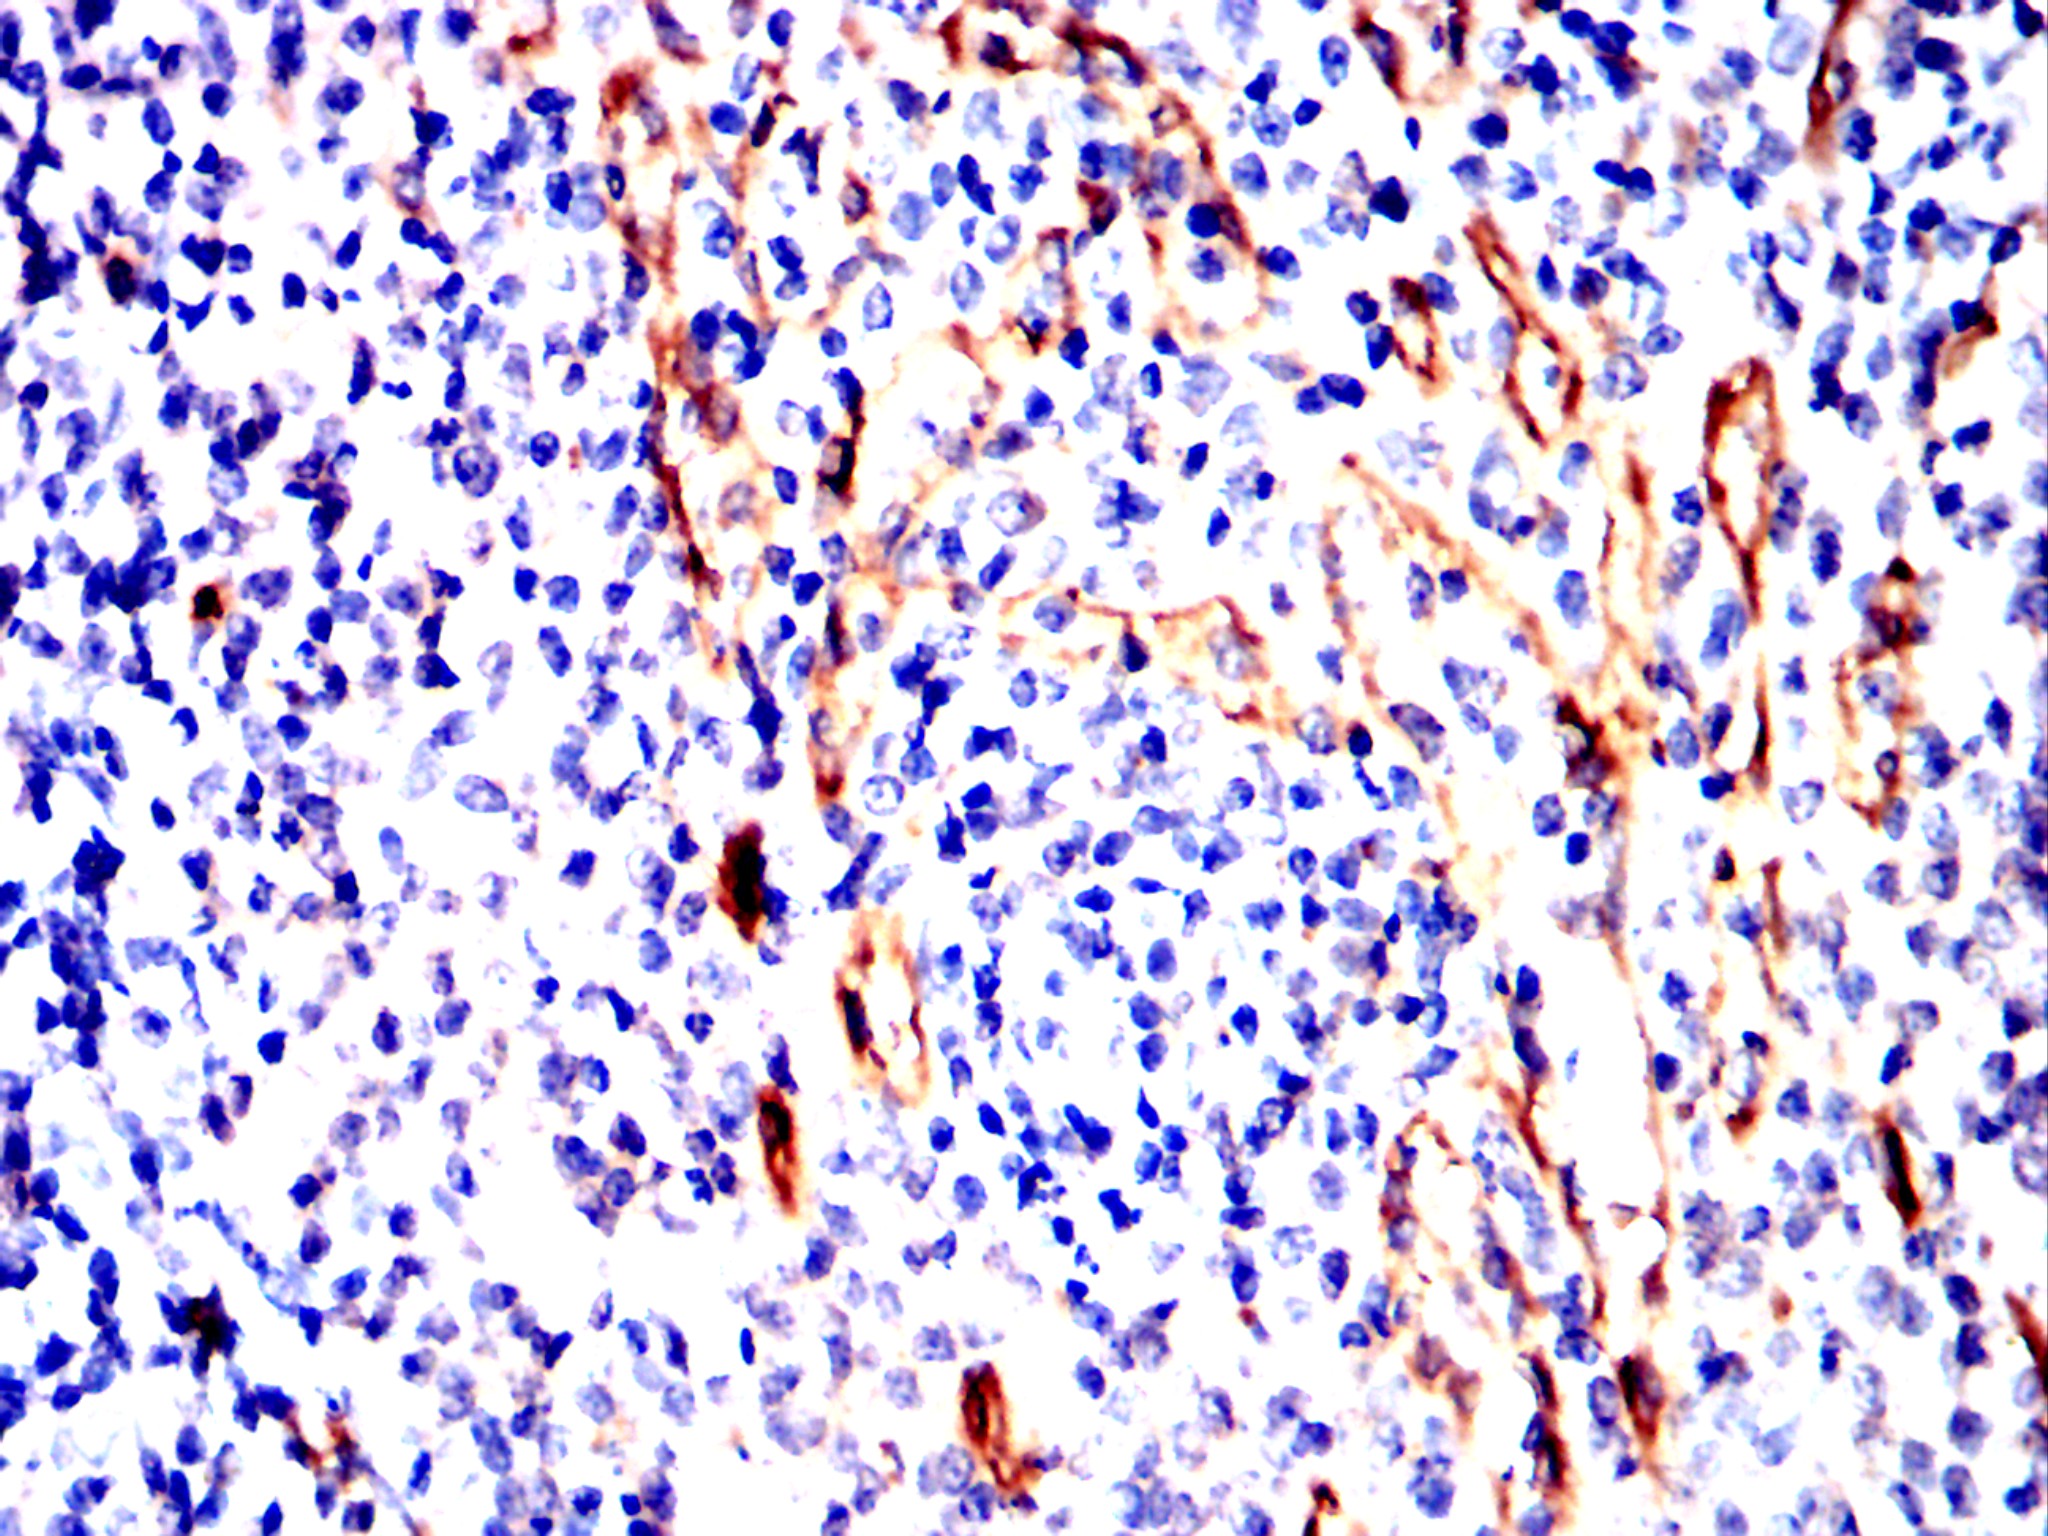

Immunohistochemical analysis of paraffin-embedded Rabbit spleen using NT5E mouse mAb with DAB staining.